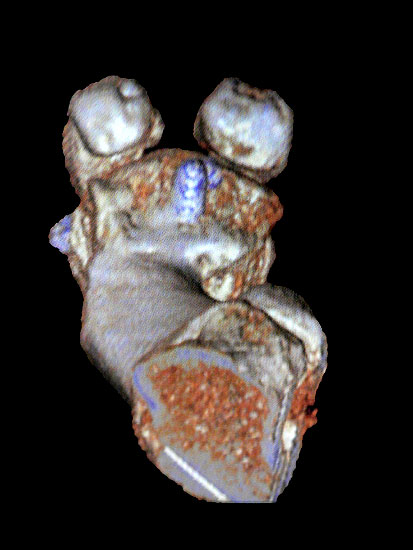

Die Röntgenaufnahmen (Abbildung 1) zeigen den Fuß einer 34 jährigen Patientin nach Exostosenabtragung. Der erhöhte intermetatarsale Winkel wurde durch eine alleinige Abtragung der Exostose nicht reduziert. Als weiterer Risikofaktor für ein Rezidiv liegt ein pathologischer Gelenkwinkel vor. Der intermetatarsale Winkel von 18 Grad kann durch eine basisnahe Osteotomie gut korrigiert werden. Da durch die gleichzeitige distale Korrektur des Gelenkflächenwinkels mithilfe einer Reverden-Green Osteotomie ein Längenverlust von ca. 2-4 mm einhergeht, bot sich als proximales Korrekturverfahren die basisnahe Open-wedge Osteotomie an, um bezüglich der Länge des Metatarsale I neutral zu bleiben (Abbildung 2). Die Kombination zweier verkürzender Verfahren (z.B. Lapidus und Reverden-Green) würden zu einem sehr kurzen ersten Strahl führen, mit dem Risiko einer Transfermetatarsalgie. Übersteigt die Verkürzung des Metatarsale I 2 mm, steigt das Risiko für die Entwicklung einer Transfermetatarsalgie deutlich an 8. Die durchgeführte Revision zeigt eine gute Stellung des 1. Strahls bei zentriert stehendem Gelenk.